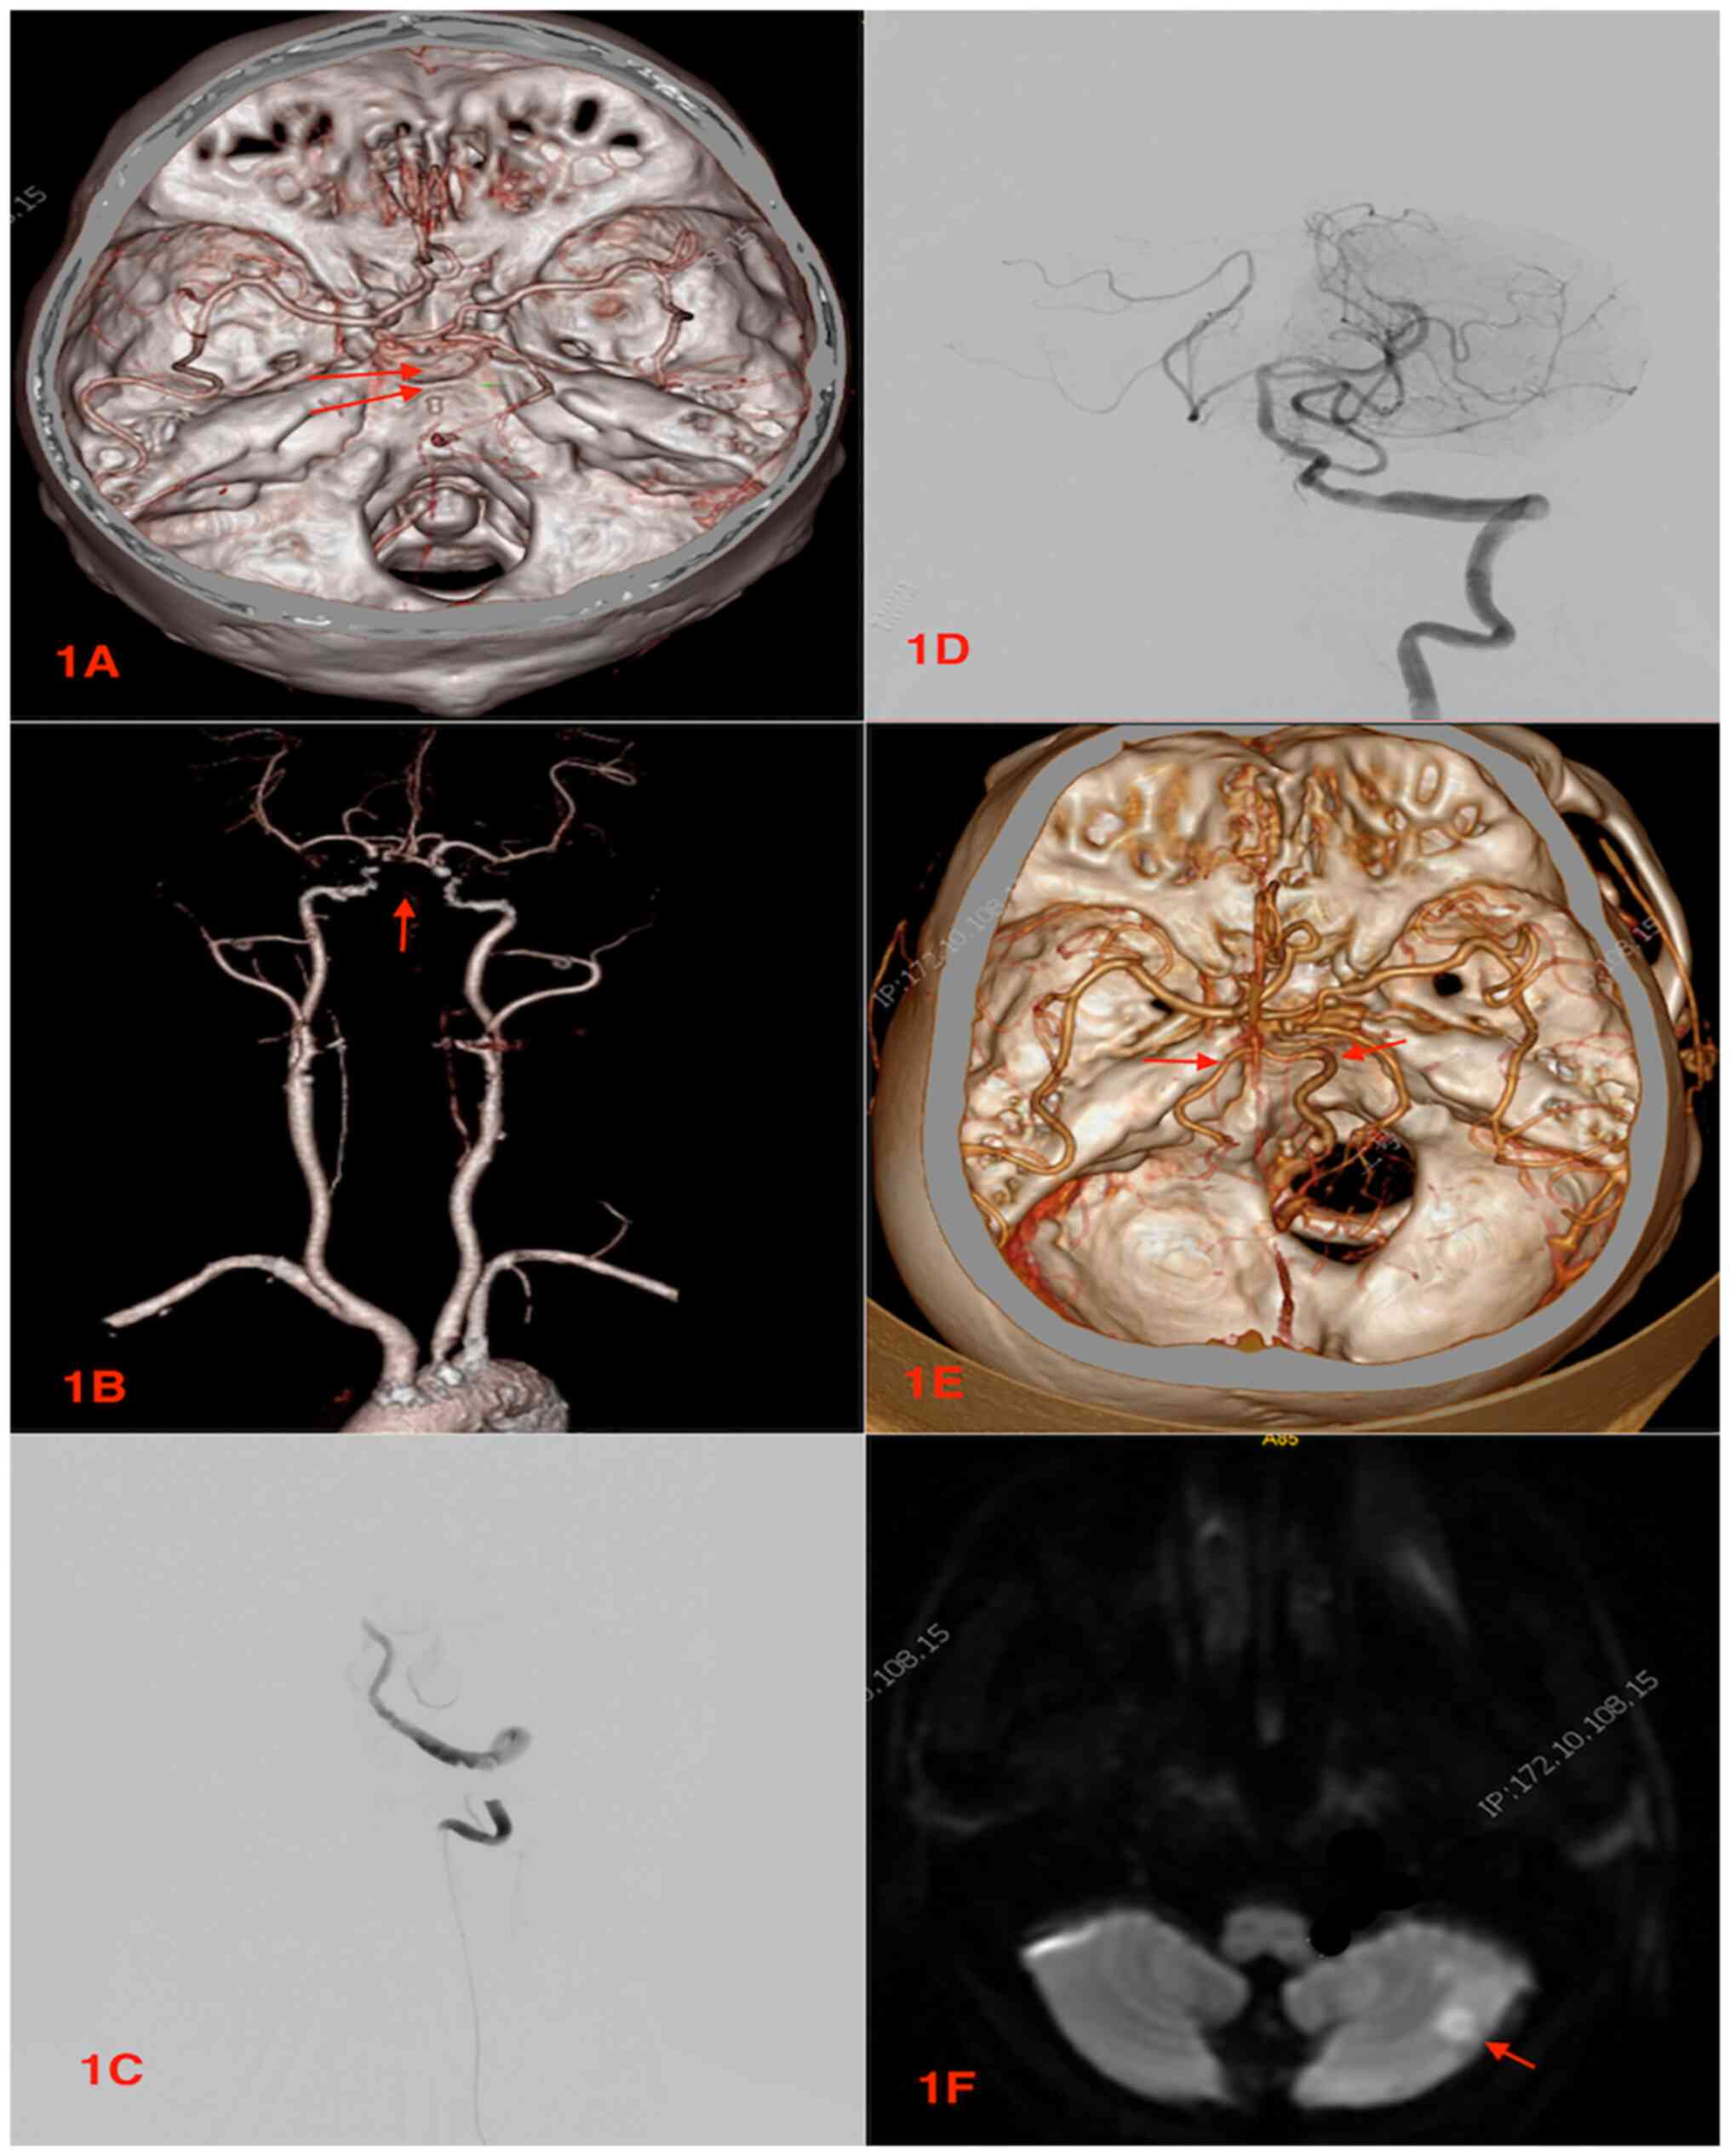

After the patient was admitted to hospital, a neurologist completed a physical examination, a neurological functional assessmen.t as well as NIHSS scoring in the emergency room. The emergency physician also performed a head CT scan to rule out intracranial hemorrhage, as well as a head and neck CTA to identify BAO (Fig. 1A and B) and/or VAO. In addition, pre-operative magnetic resonance images (MRIs) were performed in all patients to detect brainstem infarction. In all patients, the pre-operative CTA revealed the presence of large vessel occlusion, such as the BAO or VAO. The time from admission to the onset of femoral artery puncture/accesses was documented prior to the commencement of endovascular surgeries.

Figure 1

Images of one of the patients in the present study who underwent mechanical thrombectomy for basilar artery occlusion. (A-F) Pre-, intra- and postoperative images of the patient. (A and B) Pre-operative CTA images now showing no basilar artery. Red arrow indicates no basilar artery. (C) Intraoperative digital distraction angiography showing the acute occlusion of the basilar artery. (D) Intraoperative digital distraction angiography following thrombectomy showing the recanalization of the basilar artery. (E) Post-operative CTA showing the recanalized basilar artery. Red arrows indicate the basilar artery. (F) Post-operative magnetic resonance imaging showing an acute infarct in the cerebellar hemisphere. Red arrow indicates the infarction. CTA, computer tomographic angiography.

All procures were performed under general anesthesia. The entire surgical procedures were carried out strictly as previously described by Luo et al (8). After securing the femoral artery access, a 6F/8F guide catheters were maneuvered into the BA or the VAs via the subclavian arteries and initial angiographies performed to determine the locations of the occlusions (Fig. 1C). Using a coaxial system, 0.21-inch microcatheters (Rebar microcatheter; Covidien; Medtronic) and 0.014-inch microguide wires (Transend; Stryker) were advanced into the thrombi as far as the distal ends of the occluded vessels. Angiographies were then performed to confirm that the distal vasculars were patent and no pathology was found in the lumen.

In all patients, Solitaire ABs or FRs (EV3 Neurovascular) were utilized for the MT. The solitaire devices were carefully maneuvered to the occluded segments via microcatheters and the stent retrievers were unsheathed to allow for complete expansion through the thrombi. The devices often created bypasses that restored blood flow across the occluded segments. Again, angiography was performed to determine the patency of the distal arteries, after which the fully deployed the solitaire devices were resheathed. Thrombectomies were performed via the withdrawal of the solitaire devices and the delivery microcatheters as a single unit. In the case that the angiography revealed that the occluded arteries were patent (Fig. 1D), and blood flow rates were basically normal (TICI 2b and above), the procedures were then completed.

Heparin infusion was used during and immediately after the surgery. Intravenous tirofiban used during the surgery was also maintained after the surgery. Aspirin (300 mg) and clopidogrel (300 mg) were administered via the rectal route immediately after the surgery. All the patients were admitted to the intensive care unit (ICU) for monitoring and treatment, and transferred to the general ward after their conditions were stable. In all patients, immediate post-operative CT scans were performed to rule bleeding 24 h after the surgery. CTAs were also performed to confirm recanalization (Fig. 1E). In addition, post-operative MRIs were performed to assess infarctions following the procedure (Fig. 1F).